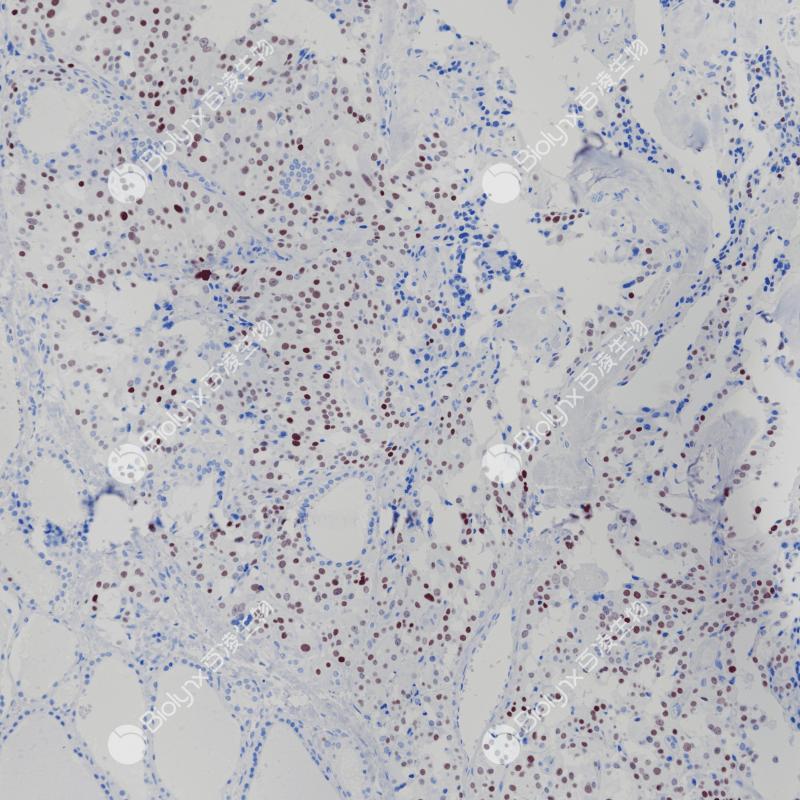

扁桃体CXCR5(BP6239)染色

CXCR5

重组兔单克隆抗体

CXCR5是一种G蛋白偶联受体(GPCR)蛋白,属于CXC趋化因子受体家族,在炎症、感染和免疫反应中起着重要作用。CXCR5在成熟B细胞和Burkitt淋巴瘤中表达,也在胃淋巴瘤的原发性和继发性滤泡中高度表达。有研究表明CXCR5/CXCL13,无论是单独使用还是联合使用,都可以作为肺癌预后的生物标志物。也有研究表明CXCR5在乳腺癌患者中过表达与淋巴结转移高度相关,CXCR5蛋白表达升高可能导致功能性p53蛋白缺失的乳腺肿瘤细胞的异常生存和迁移。